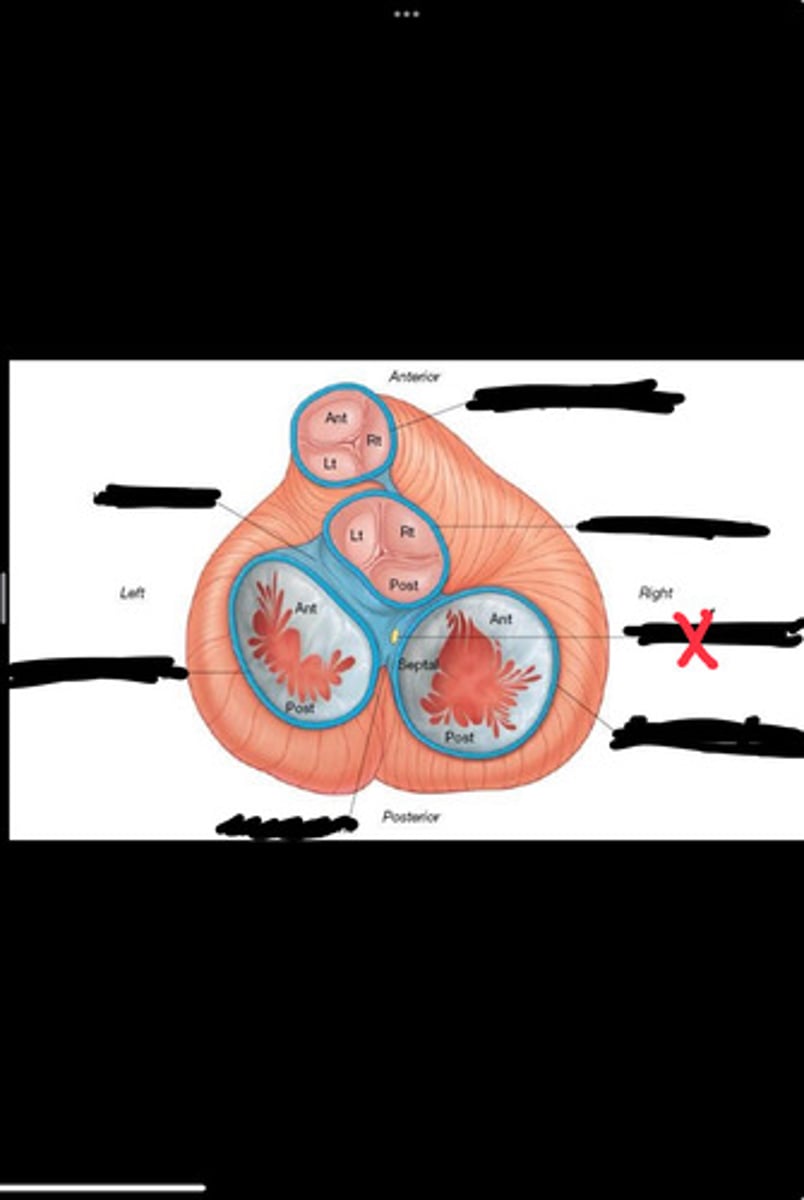

Right fibrous trigone

Left fibrous trigone

Fibrous ring of pulmonary valve

Fibrous ring of aortic valve

Atrioventricular bundle

Right atrioventricular ring

Left atrioventricular ring